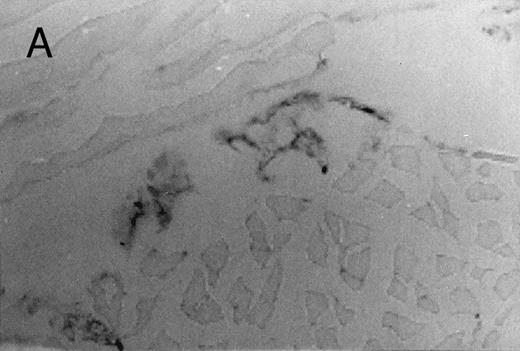

Chemotactic effect of human recombinant RANTES and MCP-1 on basophilic cells.Recently it has been reported that RANTES and MCP-1, -2, and -3 are chemotactic agents for human T lymphocytes.23 26 In this study we evaluated the selective chemotactic effects of RANTES and MCP-1 on basophilic cells. Figure 3 shows an increased number of basophilic cells after a 50 μL intradermal injection of FMLP (10−6 mol/L), RANTES 10 ng and MCP-1 10 ng, while PBS (vehicle) did not produce any appreciable effect. The infiltrated basophilic cells were colored with Toluidine blue (0.1%) and counted in the optic field using a grating of size 5 × 5 mm, under an optic microscope (× 40). In Table 2 results indicate that RANTES at 20 and 10 ng is more potent than equal doses of MCP-1 (<0.05 and 0.01, respectively). The highest number of basophilic cell accumulation in the skin injection sites was obtained with LPS (10 ng/50 μL) (193 ± 21), while FMLP (10−6 mol/L) (127 ± 14) was found to be less effective.

Basophilic cell migration induced by human recombinant RANTES 10 ng (C) and MCP-1 10 ng (D) into sites of injection. The sections were stained with Toluidine blue (0.1%) and analyzed at a magnification of ×40 (Nikon Diaphore). (A) represents a control and (B) is a positive control where FMLP was used at 10−6 mol/L. This representative experiment was found to be reproducible and has been performed at least three times.